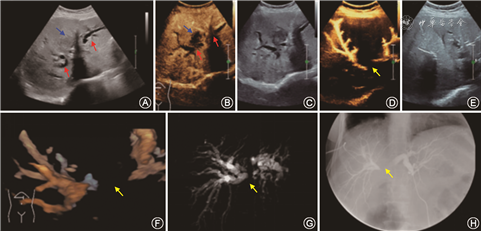

45例肝门部胆管癌患者:US诊断准确34例,误诊11例,包括1例Ⅰ型、2例Ⅲa型因肝右叶胆管扩张不明显未能准确评估受侵胆管误诊为Ⅱ型(图1),3例Ⅱ型因为肝右叶胆管伴胆泥沉积误诊为Ⅲa型,2例Ⅲb型亦因为伴胆泥沉积误诊为Ⅳ型,3例Ⅳ型由于观察不仔细误诊为Ⅲb型;CEUS诊断准确的37例,误诊8例,其中2例Ⅱ型和1例Ⅲb型都因为患者肠气影响部分肝内胆管未能清晰显示被误诊为Ⅲa型,2例Ⅱ型、2例Ⅲa型及1例Ⅳ型因为胆泥沉积、胆管扩张走行不连续被误诊为Ⅲb型;UG-PTC+3D-USC确诊42例,误诊3例,包括1例Ⅲa和1例Ⅲb因为患者脂肪较厚、肋间较窄很难准确追踪到外周胆管中断位置误诊为Ⅱ型,1例Ⅲb由于伴外周胆管胆泥沉积造成不全梗阻误诊为Ⅳ型。以X线胆管造影为诊断金标准,US、CEUS、DCUS对肝门部胆管癌分型诊断符合率分别为:75.6%(34/45)、82.2%(37/45)和93.3%(42/45)。与US相比,CEUS对肝门部胆管癌分型诊断差异无统计学意义(χ²=0.600,P=0.438),DCUS对肝门部胆管癌分型诊断差异有统计学意义(χ²=5.414,P=0.039)。

本研究发现CEUS和DCUS对肝门部胆管癌的分型诊断准确率均高于US。肝门部胆管癌中的管壁浸润型及结节型往往由于病灶沿管壁走行,存留胆管腔面积较大,梗阻上段胆管扩张不明显,往往易低估分型,而乳头型和硬化型由于梗阻程度较完全,常伴胆泥沉积,易高估分型。这与许尓蛟等[6]的研究结果US、CEUS、UG-PTC、CEUS+UG-PTC对肝门部胆管癌分型诊断准确率依次为73.3%、90.0%、86.7%、96.7%一致,可能因为增加了扩张胆管与周围感组织和其他脉管结构的声阻抗差异,易于显示梗阻端形态与其下属的各级胆管(图1)。DCUS对胆管癌分型准确率(93.3%)比CEUS(82.2%)略高,原因是DCUS弥补了CEUS间接成像缺陷、UG-PTC的二维空间缺陷、3D-USC对肝内4级以下胆管的显示不佳缺陷,可以实现图像实时三维旋转、胆管腔内及腔外改变,从而更准确地评估梗阻部位、梗阻程度及其侵犯的分支胆管、胆管树的解剖,有助于部分肝门部胆管癌患者术前提供个体化引流及精准外科手术治疗,特别是肝脏切除术前甚至在术中准确的划定手术风险、切除范围等,一定程度上降低肝门部胆管癌复发率、胆漏的发生率。而Urade等[7]提出术中超声胆道造影能准确提供可视化胆道树解剖,实时胆道导航。